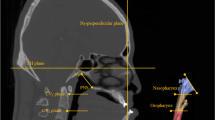

CBCT

CBCT scans were obtained before (T0) and after (T1) orthodontic treatment using a NewTom Scanner (Marburg, Germany) with the following parameters: axial slice thickness, 0.3 mm; field of view, 13 cm × 17 cm; and scan time, 15 s. During scanning sessions, patients sat upright; they were instructed to bite in centric occlusion and breathe normally without swallowing. Each patient’s natural head position was adjusted by an experienced radiologist to ensure that the orbital-auricular plane was parallel to the floor. All CBCT data were exported into DICOM format and analysed using Dolphin 3D Imaging software (version 11.8, Dolphin Imaging and Management Solutions, Chatsworth, Calif). CBCT images were oriented as follows: the horizontal plane passed through the left/right orbitales and the right porion; the sagittal plane passed through the nasion and anterior nasal spine. The coronal plane was perpendicular to both horizontal and sagittal planes. Lateral cephalographs were reconstructed from CBCT scans using Dolphin 3D Imaging software for hyoid measurement and cephalometric analysis.

The oropharynx in CBCT was defined as the region from the plane passing the posterior nasal spine to the plane passing the tip of the epiglottis [17]. The volume and the most constricted axial (MCA) area of the oropharynx were calculated (Fig. 1A). Airway segmentation threshold values ranging from 50 to 70 were adjusted to discriminate soft tissue from the airway. As shown in Fig. 1C and D, the anterior-posterior (AP) diameter, lateral diameter, and ratio of AP/lateral diameter were also measured at the level of the PNS plane and the tip of the epiglottis (E) to analyse the morphology of the oropharyngeal airway.

Measurements of oropharynx size and hyoid bone position. A Volume and most constricted axial (MCA) area of the oropharynx. B Five hyoid bone measurements: H-Eb (1), H-C3 (2), H-Me (3), H-X (4), and H-Y (5). C Anterior-posterior (6) and lateral (7) diameters of the oropharynx at the level of the PNS plane. D Anterior-posterior (8) and lateral (9) diameters of the oropharynx at the level of the epiglottis tip